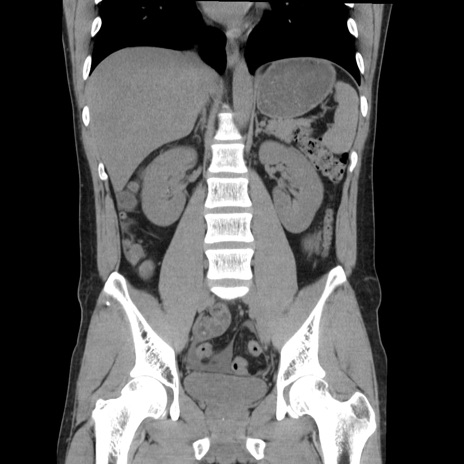

症例36(冠状断像)

【症例】20歳代 男性

【主訴】心窩部痛

【現病歴】今朝より上腹部痛あり。一旦軽快していたが再度出現したため救急要請。昨日夕に白身の魚を含む刺身を食べた。

【身体所見】BP 136/89mmHg、HR 74/min、BT 37.0℃、腹部:膨満、軟、心窩部に圧痛あり。反跳痛なし、筋性防御なし、腸雑音やや亢進あり。

【データ】WBC 17700、CRP 0.48